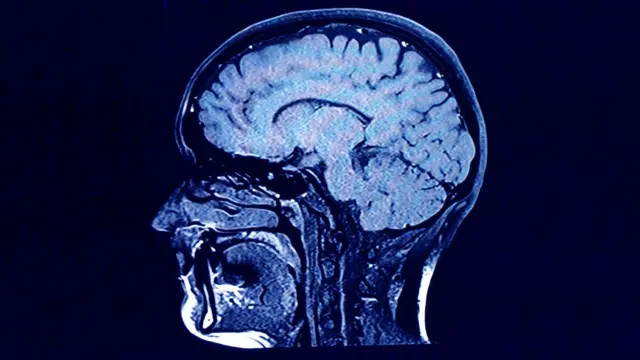

En 2013, el equipo también recurrió al pico de la bomba para observar la rotación de las células cerebrales.

Durante muchos años, los investigadores asumieron que la cantidad de neuronas se consolidaba en la infancia y, de hecho, su investigación anterior ya había sugerido que ese era el caso en regiones como la corteza.

Sin embargo, mediante el uso de carbono-14 para datar las neuronas dentro del hipocampo, confirmaron que se pueden producir nuevas neuronas a lo largo de la vida adulta.

Corroborada por otras investigaciones, la posible existencia de "neurogénesis adulta" ha sido uno de los descubrimientos neurocientíficos más importantes de los últimos 20 años.

Esto ha sugerido nuevas vías hacia estrategias médicas que podrían prevenir la pérdida de neuronas por enfermedad o incluso aumentar la generación de nuevas.